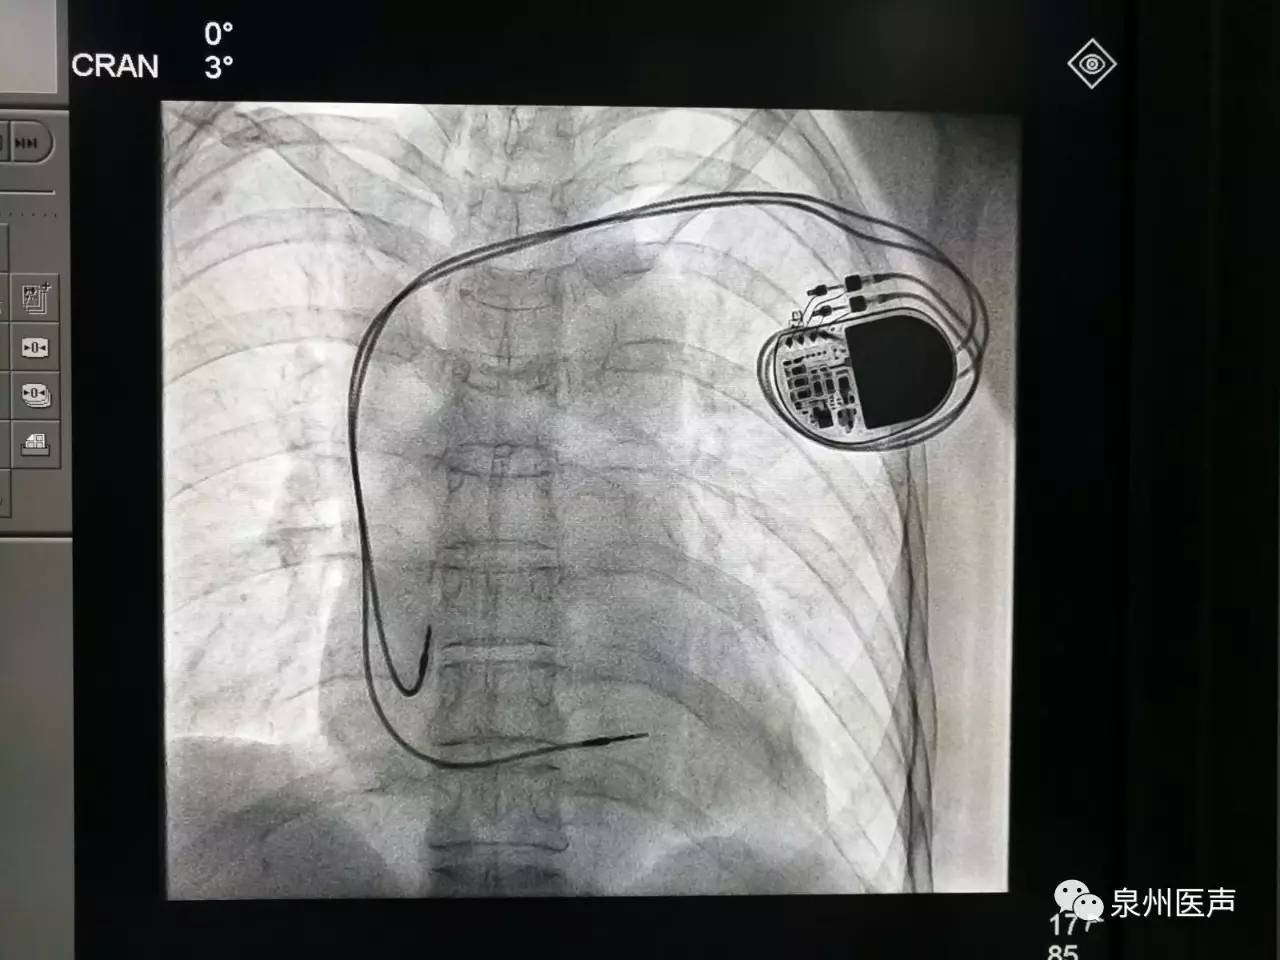

微創(chuàng)、樂普、先健填補國產(chǎn)起搏器市場空白,釋放哪些信號?

世界最小起搏器,正式進入中國市場!

器械之家曾做過專題報道的“世界最小起搏器”(嬰兒用除外)在經(jīng)過了漫長的中國本土臨床研究后,終于獲得NMPA批準,正式于中國上市!

最高級別!美敦力緊急召回1.3萬個雙腔植入式心臟起搏器!

美敦力公司因可能的電路問題,將召回超過1.3萬個雙腔植入式心臟起搏器。FDA確認此次召回為最嚴重的一類召回,使用該醫(yī)療器械可能或?qū)⒁饑乐亟】滴:Α?/p>

心臟起搏器的日常護理

心臟起搏器出院的宣教,是心內(nèi)科醫(yī)護人員不容忽視的一項工作